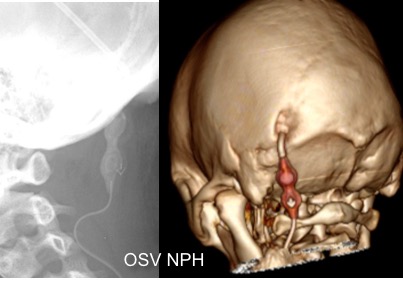

il existe un grand nombre de valves ; il n’est pas toujours aisé de les reconnaitre radiologiquement. voici la liste des plus courantes :

comment reconnaitre radiologiquement le type de valve ?

il est important pour le radiologue qui fait une IRM quel est le type de valve en raison des implications sur l’image et sur le fonctionnement de la valve (en pratique ce surtout les anciennes sophysas ancien modèle qui se dérèglent dans l’IRM).